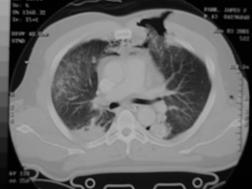

Contuzie pulmonara stanga Contuzie pulmonara dreapta

Contuzie pulmonara dreapta.Imagine CT

(stanga) Contuzie pulmonara (dreapta)